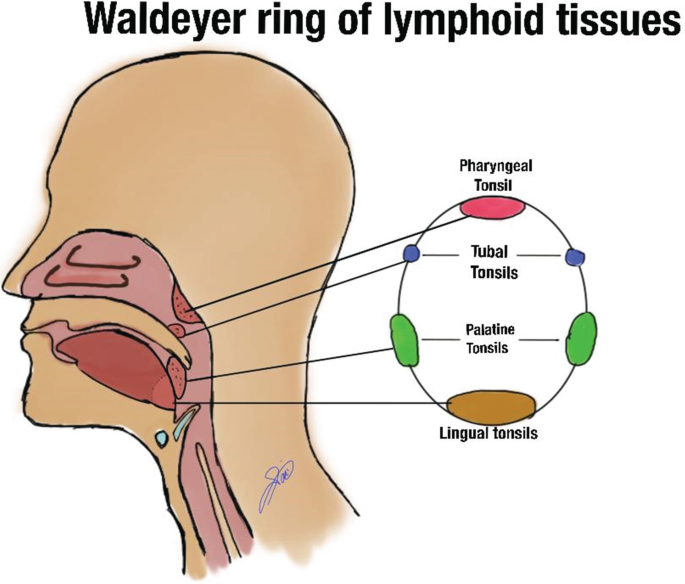

Tonsil

Waldeyer’s tonsillar ring

Nasopharynx

- Pharyngeal tonsil

Oropharynx

- Palatine tonsil